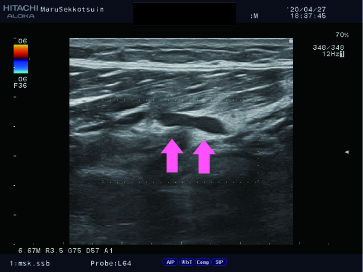

今日もハムストリングスの肉離れで御来院。。。